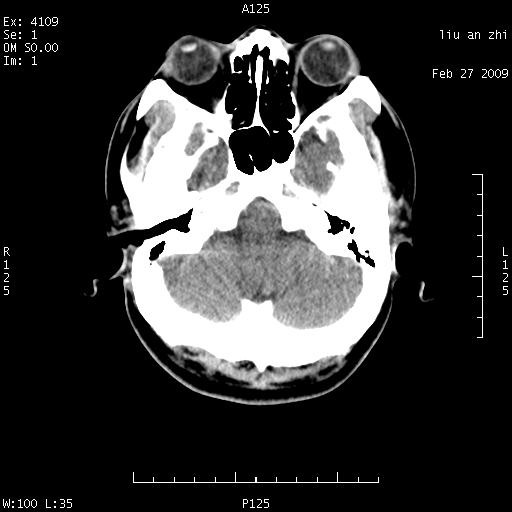

患者:男,32岁 被打伤后3天,自感头昏头痛作头颅ct检查。请大家看一下想什么??

请注意小脑幕!!!

ct18448的结果:mri检查左侧天幕下血肿

以下是引用深蓝一号在2009-3-9 16:22:00的发言:[br]ct18448的结果:mri检查左侧天幕下血肿。